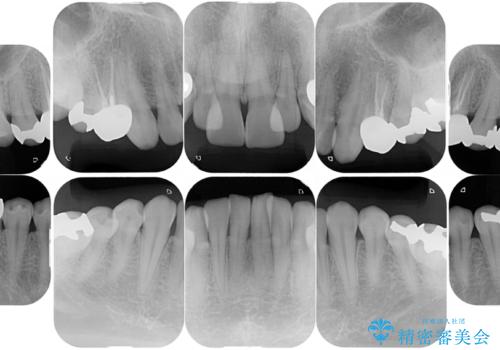

元々噛む力が強く、日常的に歯ぎしりもされるとの事でしたので、歯が割れてしまうリスクを軽減させるため、歯全体を覆うクラウンをメインに補綴治療を行いました。

適合不良の補綴物は二次的な虫歯発生のリスクが高まります。

自費診療で用いられる材料は保険適応の材料に比べて、より精密で適合の良い被せ物作ることができるため、長期的な虫歯のリスクを大幅に減らすことが可能です。